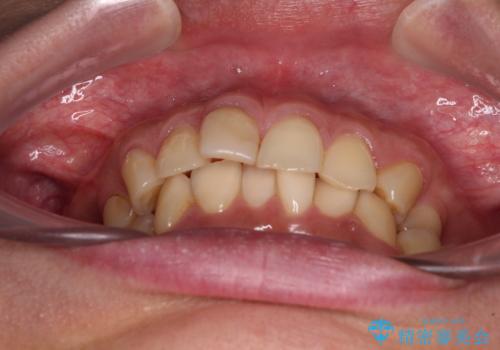

- 全体的なデコボコと左下乳歯部の欠損を気にして来院された患者様です。

乳歯が抜け落ちた後の後続永久歯が欠損しているため、スペースが残っておりました。

口元の突出感を気にしているのであれば欠損スペースを利用して抜歯矯正を行うことも可能ですが、横顔の印象はスッキリとしている状態であったため、矯正治療でスペースを閉じきることは不可能と判断し、インプラントによる補綴治療を行うこととしました。

第二小臼歯の欠損によるが乳歯残存や欠損が多く、この乳歯は後続永久歯に比べて幅が非常に大きいため、教聖地料によるスペースクローズが難しいことが一般的です。